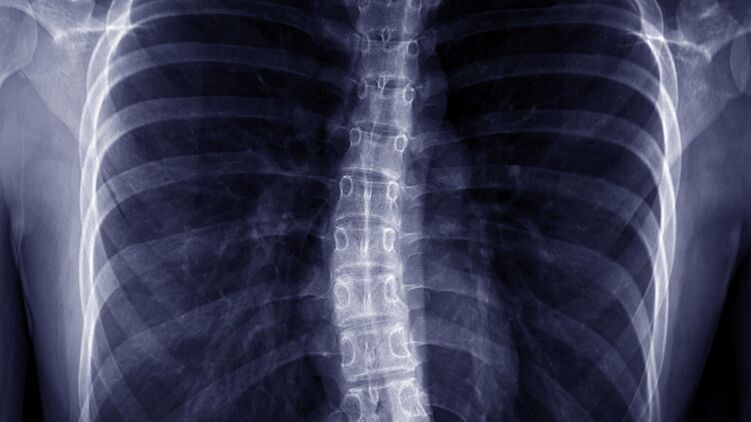

Этот недуг характеризуется S или C образным искривлением позвоночника в боковой плоскости. Человек может выглядеть так, будто он наклоняется в одну сторону. При этом могут поражаться как грудной, так и поясничный отдел позвоночника.

С увеличением искривление растет тенденция к ухудшению проблем общего состояния здоровья. Сильные сколиозы является причиной деформации туловища и его укорочения и приводят к уменьшению объема грудной клетки и брюшной полости.

- заметно изогнутый позвоночник, склонен в одну сторону